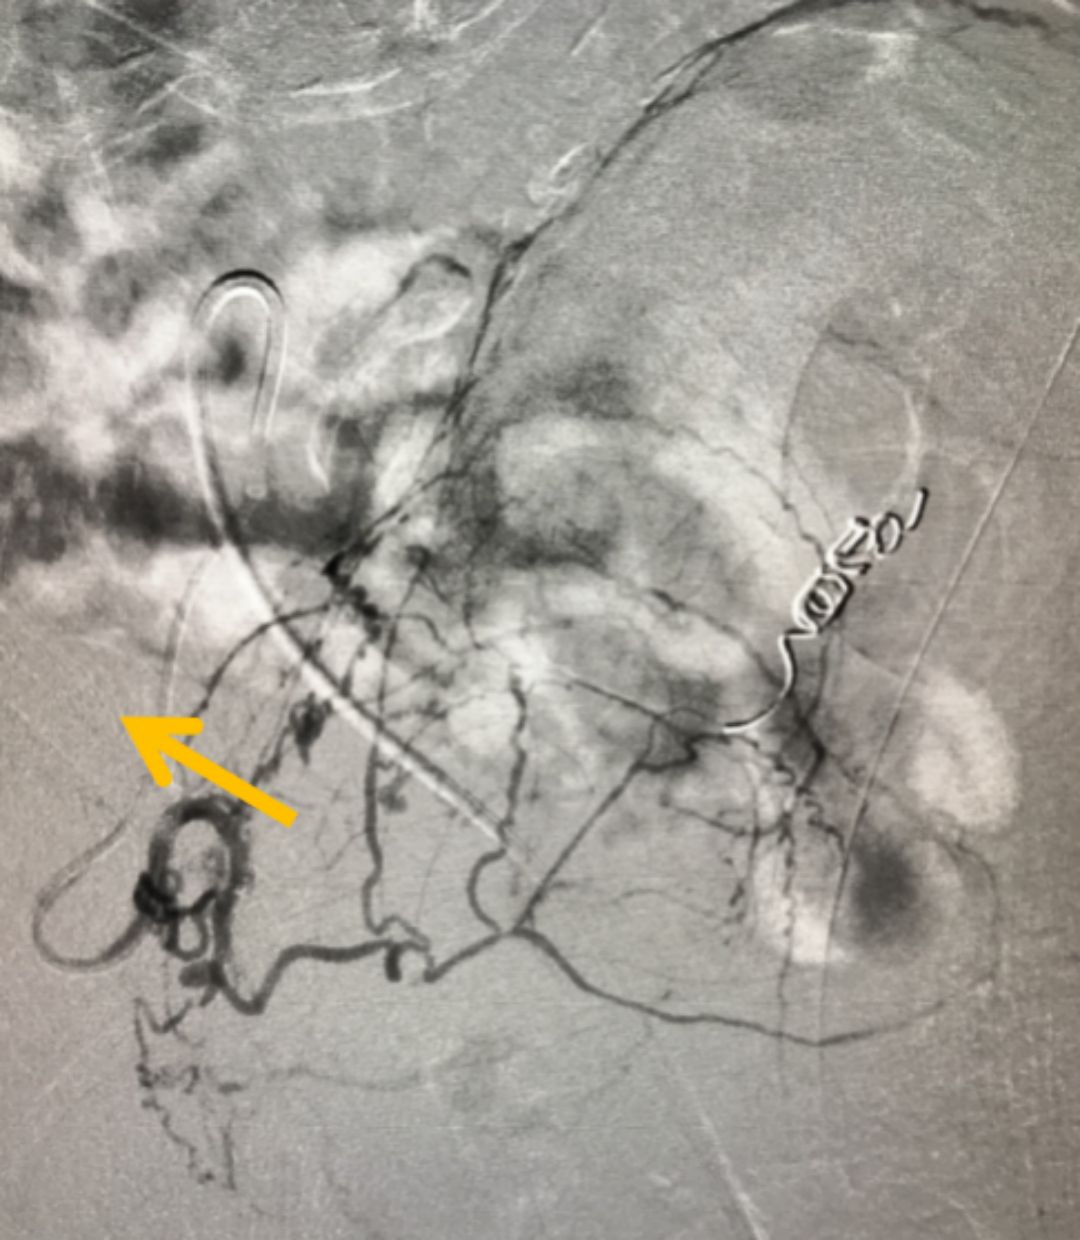

在全面評估后,團隊為他制定了PAE的精準(zhǔn)治療方案。手術(shù)僅通過大腿根部一個針眼大小的穿刺點,將比頭發(fā)絲還細的微導(dǎo)管,在影像引導(dǎo)下精準(zhǔn)送入供養(yǎng)前列腺的動脈,并注入安全的栓塞微粒。這個過程,就像精準(zhǔn)地“斷糧”

圖:微導(dǎo)管(箭頭所指)

增生的前列腺組織需要充足的血液供應(yīng)才能維持“生長”。PAE技術(shù)的核心,就是阻斷這些供給增生的“營養(yǎng)通道”,從而讓過度增殖的組織因“饑餓”而自然萎縮、壞死,解除對尿道的壓迫。